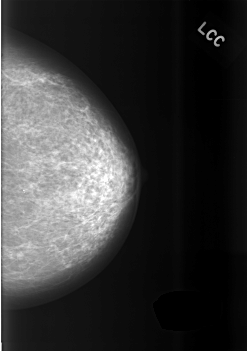

C_0475_1.LEFT_CC

LEFT_CC LINES 5616 PIXELS_PER_LINE 3944 BITS_PER_PIXEL 12 RESOLUTION 50 NON_OVERLAY